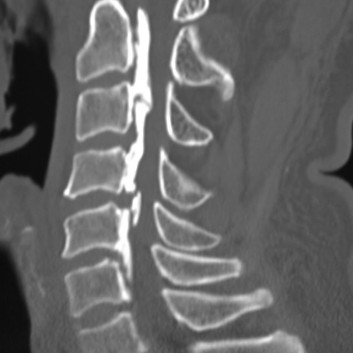

경추 척추관 협착증

여러 원인에 의해 척수가 지나가는 중심관이 좁아져 몸의 가장 중요한 신경인 척수를 압박하게 되어 목, 어깨, 팔, 손 등에 통증이 나타나게 되는 것을 말합니다. 심할 경우 다리에 힘이 빠지는 증상까지 나타날 수 있습니다.